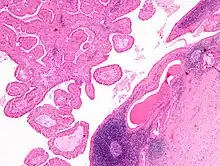

This Warthin's tumor presented as a parotid mass in a middle-aged male, who underwent superficial parotidectomy. The tumor, at the right of the image, is well-demarcated from the adjacent parotid tissue and tends to shell out from it.